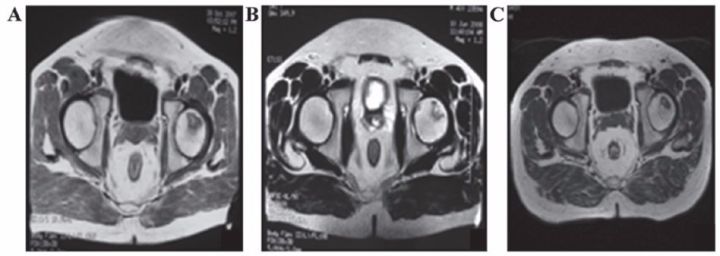

7、運動系統疾病

?股骨頭壞死

間充質干細胞移植治療人體股骨頭壞死在國外已有報道。法國科學家移植治療116例股骨頭壞死患者效果顯著,其中87.3%的患者髖關節疼痛緩解;78.4%的患者關節功能改善;80%的患者行走間距延長。

吉林一位許姓小伙在一次攀巖活動中從高處摔下來,送到醫院檢查,雙側股骨頭已壞死變形。按照常規治療方法,應行人工關節置換手術。可是人造股骨頭的壽命一般在10-15年,小許才27歲,一輩子需要不停地更換人工關節。

沈陽463醫院的楊曉鳳主任將間充質干細胞經過技術處理后注入小許的股骨頭,兩周后小許就可以下地行走了。10個月后,小許來醫院復查,他的股骨頭周圍已長出豐富的血管,表明移植的間充質干細胞促使壞死變性的股骨頭修復新生。

表8 劉穎、谷涌泉應用臍帶MSC治療股骨頭壞死的臨床研究結果

吉林省組織工程重點實驗室劉穎教授 、首都醫科大學宣武醫院谷涌泉主任等,對9位骨循環協會評級為II-IIIa級的股骨頭壞死患者經大腿動脈輸注臍帶間充質干細胞后,患者的紅細胞、血小板、血氧轉運指數明顯改善。MRI檢測顯示24個月后股骨頭壞死區域體積顯著減少。